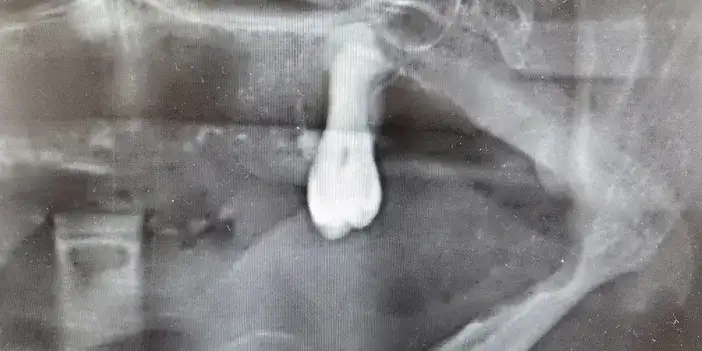

Ağız kanserinde erken tanı gerçekleşirse hastaların ölümle sonuçlanmasının önüne geçilebileceğini ifade eden Prof. Dr. Gündüz, “Biz kurum olarak Karadeniz'in en büyük üniversitesiyiz ve de fakülte olarak da Karadeniz'de büyük bir hizmet vermekteyiz. Ortalama yaklaşık günde 500 hasta, aylıkta 10 bine yakın hasta bakıyoruz. Biz yapmış olduğumuz seminerlerde hem öğrencilerimizi hem asistanlarımızı hem de halkımızı bu konuda bilgilendirmeye çalışıyoruz. Erken tanı eğer gerçekleşirse bu hastalıkların ölümle sonuçlanmasının nispeten önüne geçmiş oluyoruz. Çünkü erken tanı biliyorsunuz her kanser vakasında çok önemli bir yer tutmakta. Herhangi birisi ağzında eğer 2 haftanın üzerine geçmeyen bir yara varsa mutlaka en yakın diş hekimine başvurması gerekmekte. Sebepsiz yere dişlerin sallanması, uyuşukluk olması, yüzde sebepsiz ağrıların, çene bölgesinde sebepsiz ağrıların oluşması kanserlerin başlangıç bulguları arasındadır. Zaten kanserlerin en fazla oluştuğu yerler ağız içerisinde dilin özellikle arka kenarlarıdır. Bunlar ne yazık ki başlangıçları da ağrısız olduğu için bir kısmının gözden kaçabilmekte. O yüzden insanlarımızdan, halkımızdan bu konuda dikkat etmeleri, eğer böyle bir lezyonla muhatap olurlarsa mesela bir yakınından ağız içerisindeki görüntüsünü çekmesini talep etmeli. 2 hafta sonra da aynı şekilde bu görüntü duruyorsa veya daha da büyümüşse en yakın merkeze gitmesini önermekteyiz” ifadelerini kullandı.